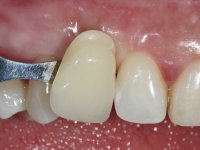

The proposed treatment results from the limitations imposed by the patient, who refused an orthodontical pull of the canine into the edntulous space, and was unwilling to extract the impacted canine and place an implant in the zone of 1.3. Thus, the confection of a Maryland Bridge was proposed, with a Zr infrastructure and two retainers. The mesial retainer would be bonded to the palatal face of the tooth 1.2 and the distal retainer was to be bonded to the palatal wall of tooth 1.4.

To define the dental zone to be covered by the Maryland bridge retainers, the patient was asked to perform maximum intercuspidation movements, and the contact points were marked with articular paper. Tooth preparation of the interproximal surfaces was made, to create a prosthetic insertion axis. It was sought that the mesio-distal diameter at the incisal level was equal to the diameter mesio-distal at the cervical level, that is to say, the interproximal walls were parallelized. Tooth preparation was done with fine grain diamond drills, and later polishing was done with abrasive discs. Color information was collected even before confection of the impression, to avoid dehydration of the arcade. Definitive impression was made using wash technique impression with silicone of heavy and regular consistency, both with fast setting, and a working plaster model was prepared in the lab. A laboratory scanner was used to scan the working model, and later, the infrastructure for the Maryland bridge was made using a CAD-CAM process. Ceramic was placed on this subframe. A ceramic adhesive was applied to the internal surface of the wings and connectors, which would enable bonding to the adjacent teeth. The adhesive bridge was bonded in the mouth following the conventional bonding technique. After bonding, the protrusion and laterality movements were carefully checked to avoid undesirable contacts.